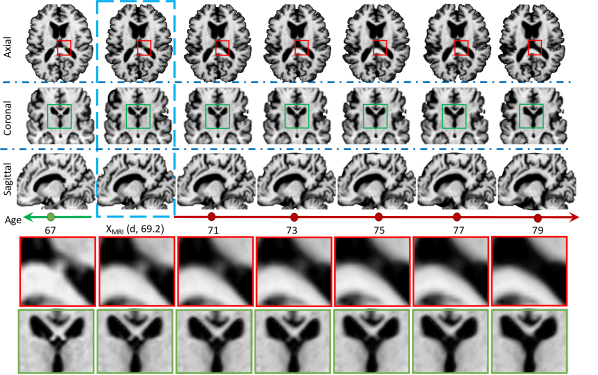

For completeness, Fig. 1 shows an example of an entire simulation obtained using the full configuration of 4D-DANI-Net. Expected neurodegeneration is apparent in the sequence, including ventricular expansion, hippocampus contraction, and cortical thinning.